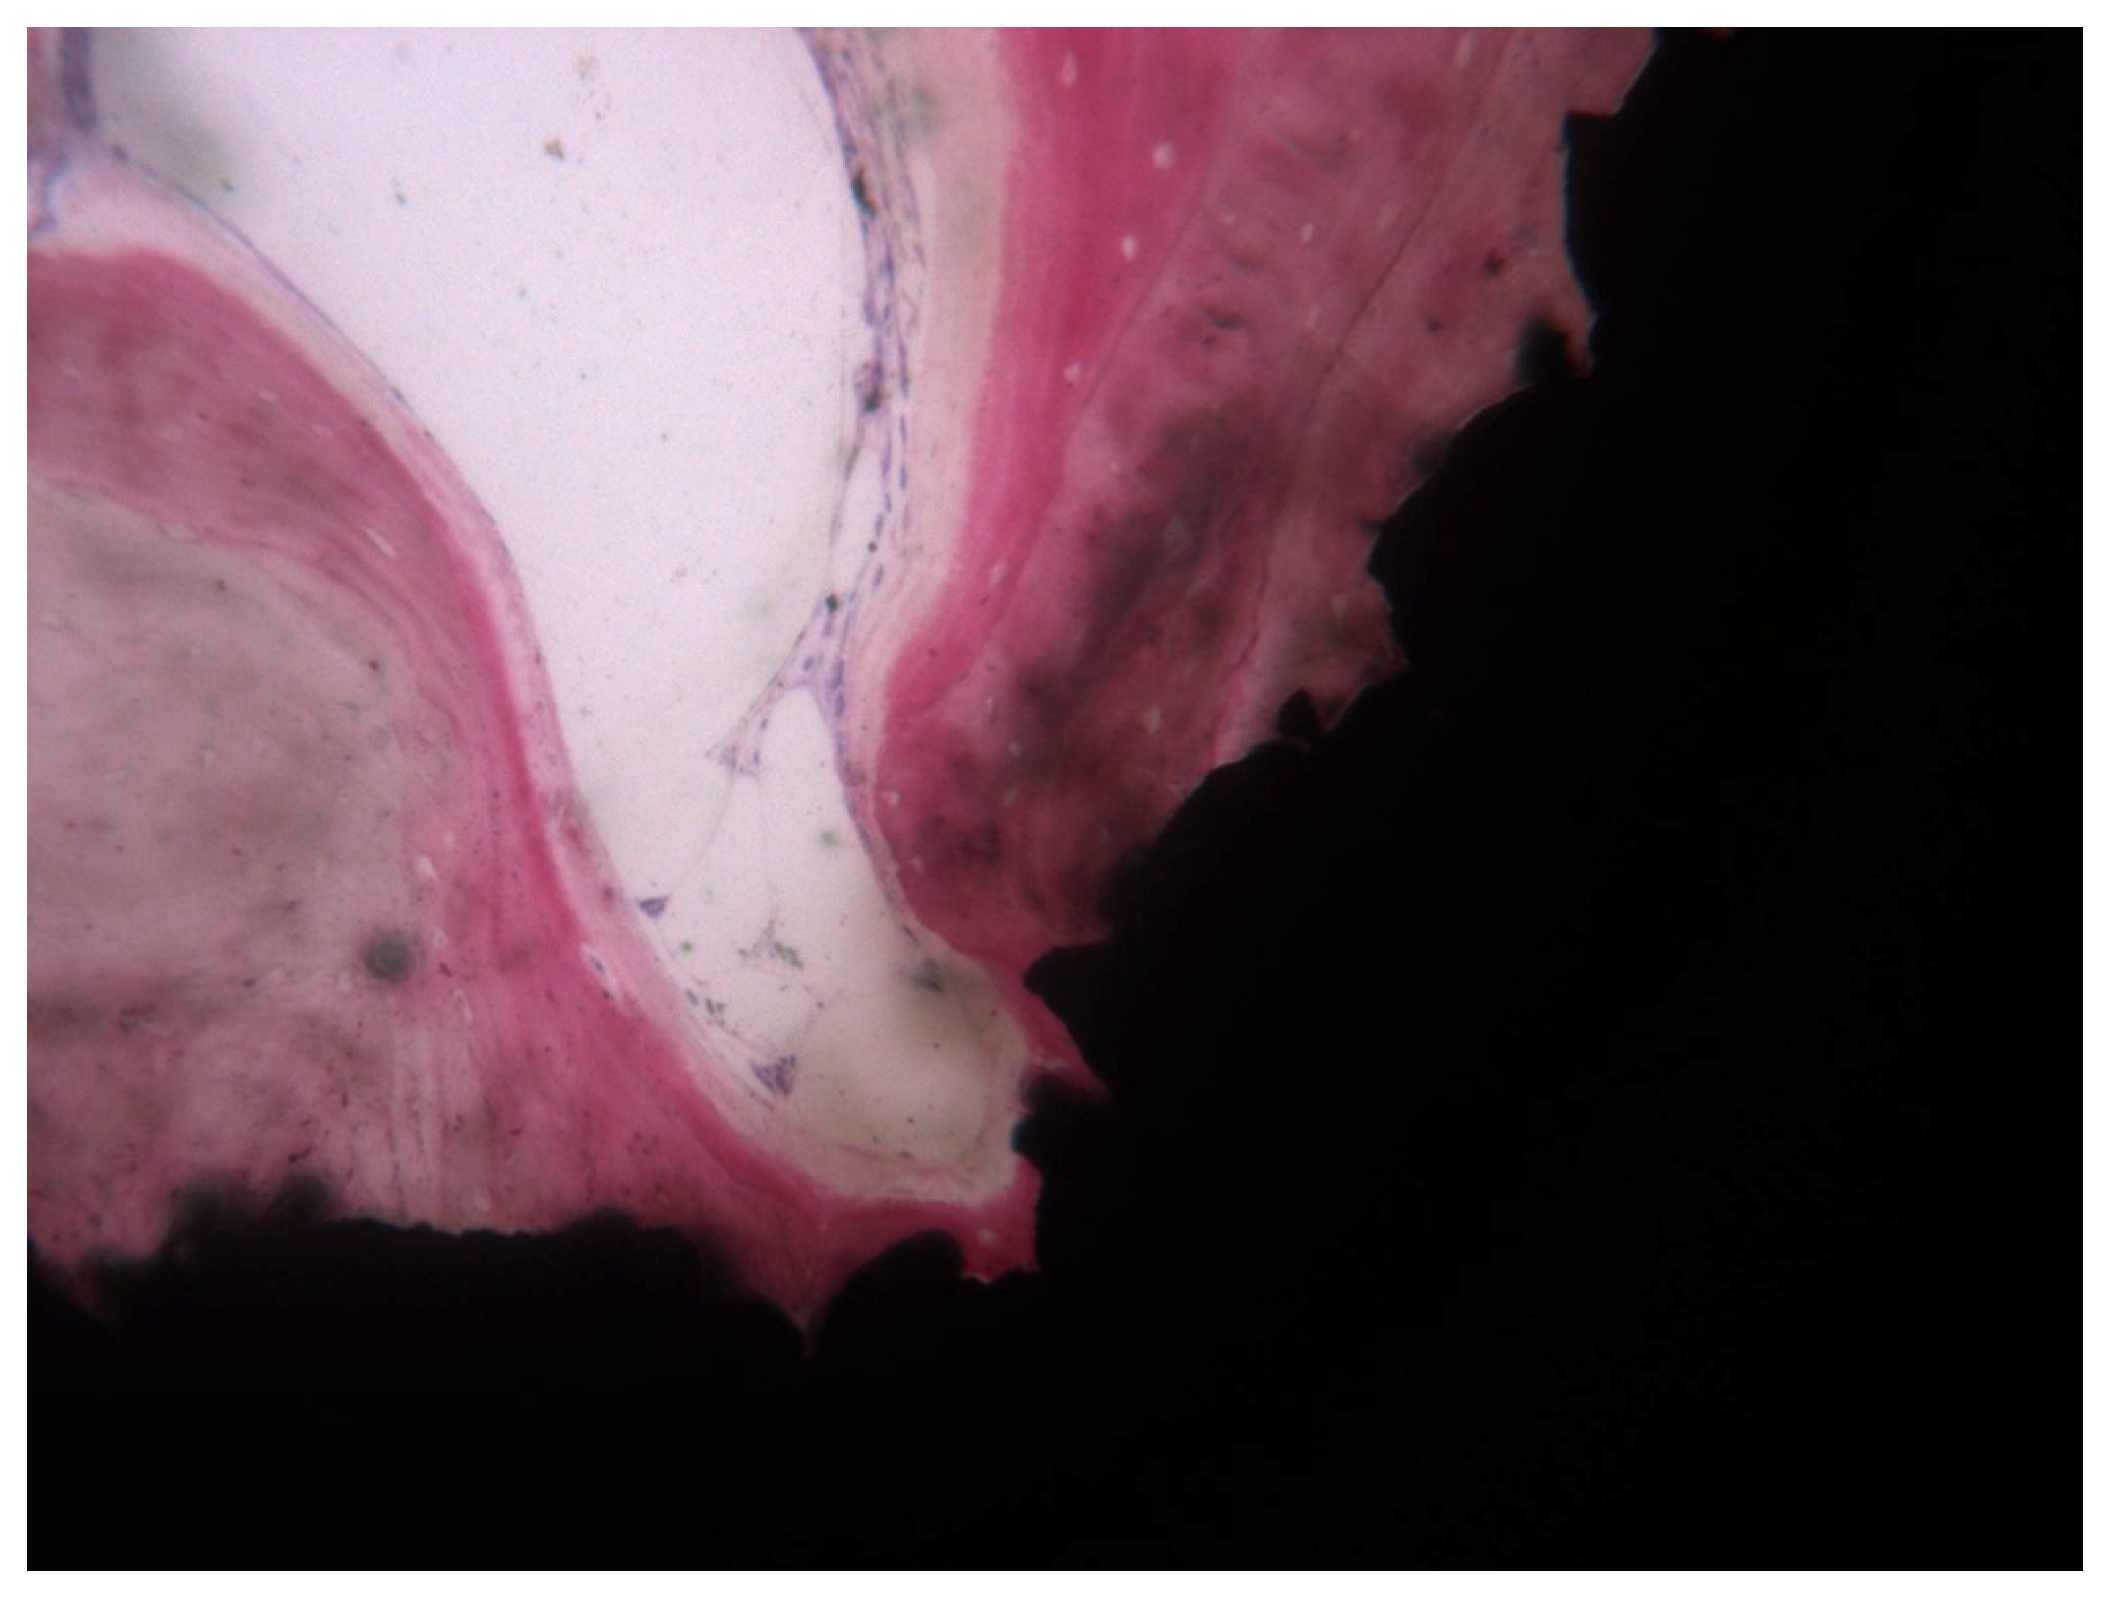

3. Results